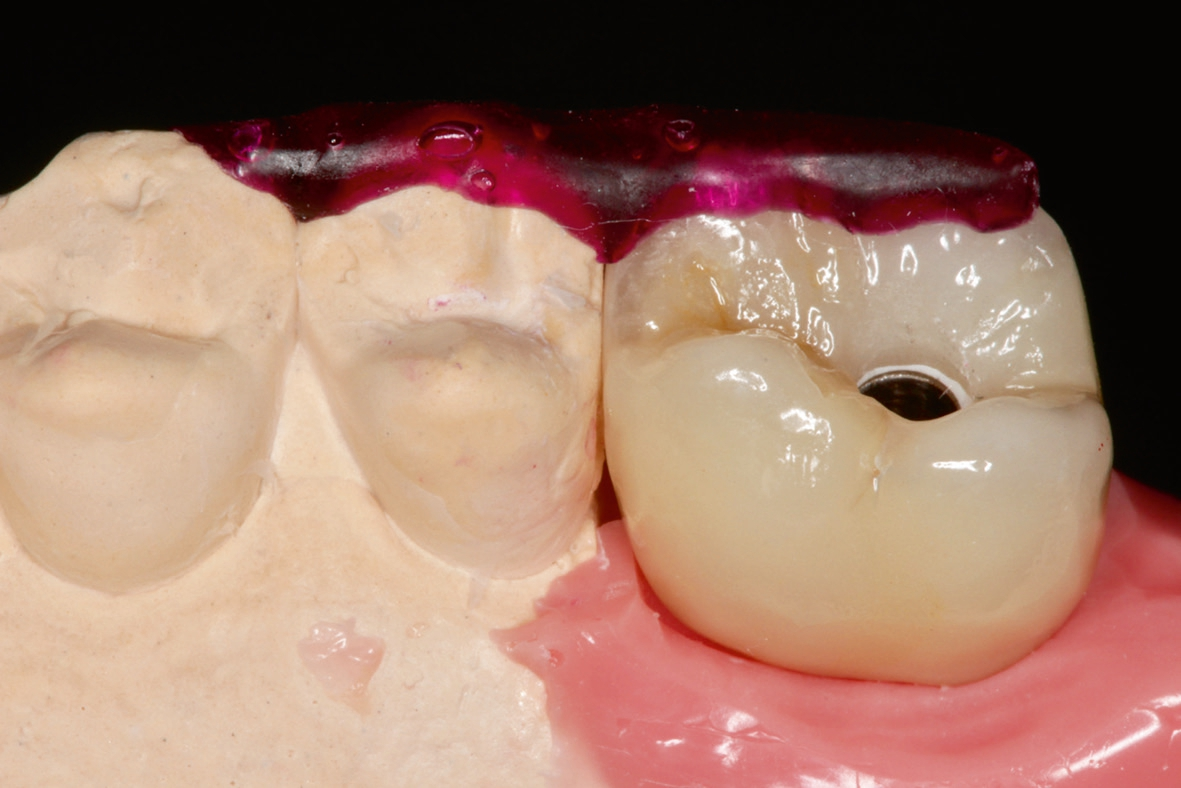

Die Übertragung der Implantatposition ins zahntechnische Laboratorium wird mittels offener Abformung mit individuellem Löffel und einem stabilen Polyäthermaterial vorgenommen. Die achsgerechte Position des Implantates ermöglichte die Anfertigung einer transocclusal verschraubten, verblendeten Zirkonoxidkrone auf einer Klebebasis. Die Besonderheit der Konstruktion ist dabei, dass das Metall der Klebebasis bei der fertigen Konstruktion komplett von Zirkon umschlossen ist. Dies erfordert eine hohe technische Präzision und eine spezielle „Verklebehilfe“ im Labor. Zur ersten Einprobe der Krone beim Patienten befestigen wir die Krone zunächst nur provisorisch auf der Klebebasis. Dies stellt sicher, dass sie bei eventuell notwendigen Korrekturen leicht gelöst und erneut gebrannt werden kann. Ist die Krone in Farbe und Form fertig gestellt, so muss sichergestellt sein, dass die endgültige Verklebung exakt in der gleichen Position auf der Klebebasis erfolgt, wie die zuvor einprobierte. Dafür fertigen wir einen Kunststoffschlüssel.